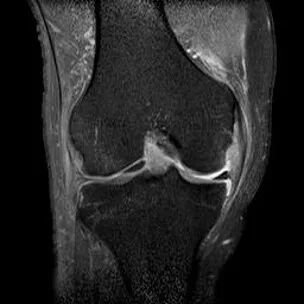

1、宽度减小,在通过半月板体部的冠状面上蝶形消失,同时可见内移的半月板位于髁间窝、交叉韧带旁2、矢状面示残余的前角或后角变小或截断3、半月板前(后)角增宽或双半月板前(后)角征4、双前交叉韧带或双后交叉韧带征

桶柄状撕裂(双后交叉韧带征)

桶柄状撕裂:双前交叉韧带征